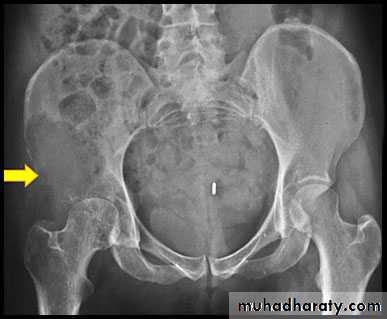

Metastases :Metastases are by far the commonest malignant bone tumor.

Metastases may be sclerotic , lytic or a mixture of lysis& sclerosis

Lytic metastases.

1- in adults most commonly arise from a carcinoma of the breast and bronchus , less commonly from carcinoma of the thyroid , kidney or colon .

Lytic metastases give rise to well defined or ill defined areas of bone destruction with out a sclerotic rim .the lesions vary from small holes to large areas of bone destruction.